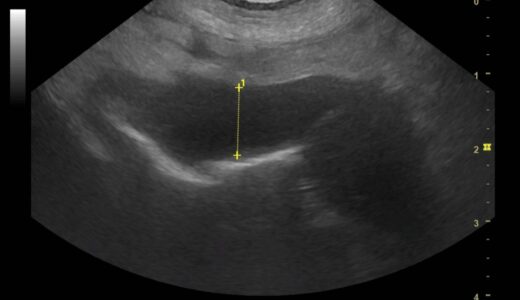

胃リンパ腫